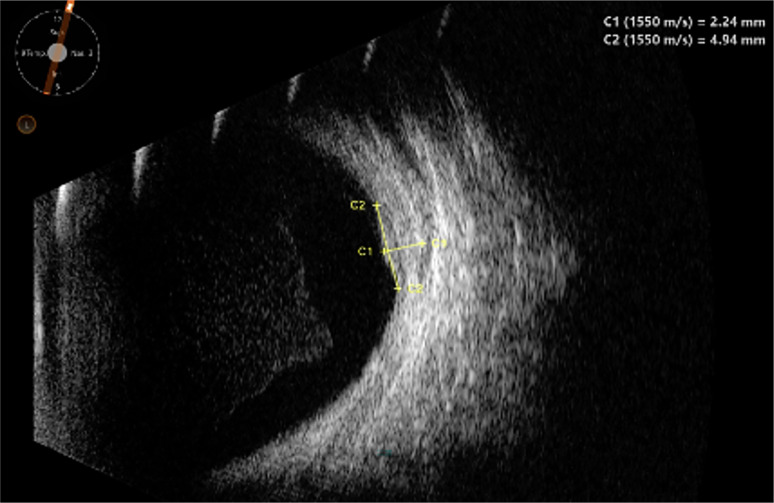

Case report: A 13-year-old female presented with pain in her left eye and no light perception in that eye. She was found to have left eye advanced neovascular glaucoma related to VPT in the context of MYO7A-related Usher syndrome. Intraocular pressure and pain were controlled with external diode cyclodestruction. Almost 3 years later, early asymptomatic VPT was noted in the right eye during follow-up and was treated with laser photocoagulation.